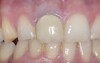

IMPLANTOLOGIE : LA PÉRI-IMPLANTITE, COMPLICATION CLASSIQUE À TRAITER SANS TARDER